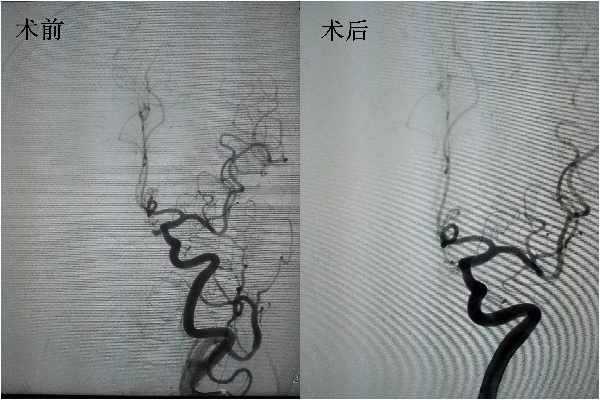

患者文某,女性,因“突发头痛1天”于10月4日由库伦旗医院转入我院治疗,入院后立即在局麻下行全脑血管造影术(DSA)检查,术后明确诊断左侧眼动脉段动脉瘤,经我院神经内三科会诊讨论,充分评估病情,患者病情诊断明确,与患者家属耐心沟通后,决定为患者在全麻下进行颅内动脉瘤栓塞术。手术由徐鹏医师主刀,韩永峰医师配合,术中遇到了微导管放置困难的情况。首先,微导管到位困难;其次,微导管固定困难。一旦微导管放置不成功,栓塞则不能进行,手术失败,患者仍有再次出血导致生命危险的可能,考虑到患者的经济费用(支架及输送设备需4万块钱左右)以及维持支架通畅需服用抗血小板聚集药物(拜阿司匹林、硫酸氢氯吡格雷),神经内三科医务人员选择只是单纯的将动脉瘤栓塞。在多次调整之后,终于将动脉瘤近完全填塞,医务人员悬着的心也终于放下了。术中患者的生命体征稳定。

据悉,对于治疗动脉瘤的方法,常规有两种,一种是经典外科手术,另一种就是介入栓塞治疗。根据该患者颅内动脉瘤特点,介入治疗及外科手术治疗难度均较大。但外科开颅手术术中需要磨掉前床突,动脉瘤方向性差,难以暴露及夹闭,夹闭过程中动脉瘤破裂,出血难以控制,并且每一次开颅手术对患者都存在继发性的打击。而介入栓塞治疗,创伤相对更小,恢复更快,术中不碰到脑组织,且占位效应小,治疗目的性更强,更有效,并且极大地减少了患者的痛苦。我院此例手术的成功开展,不仅填补了我市该项技术的空白,也为广大患者带来了福音,标志着我院神经内科介入手术技术已达到了自治区领先水平。